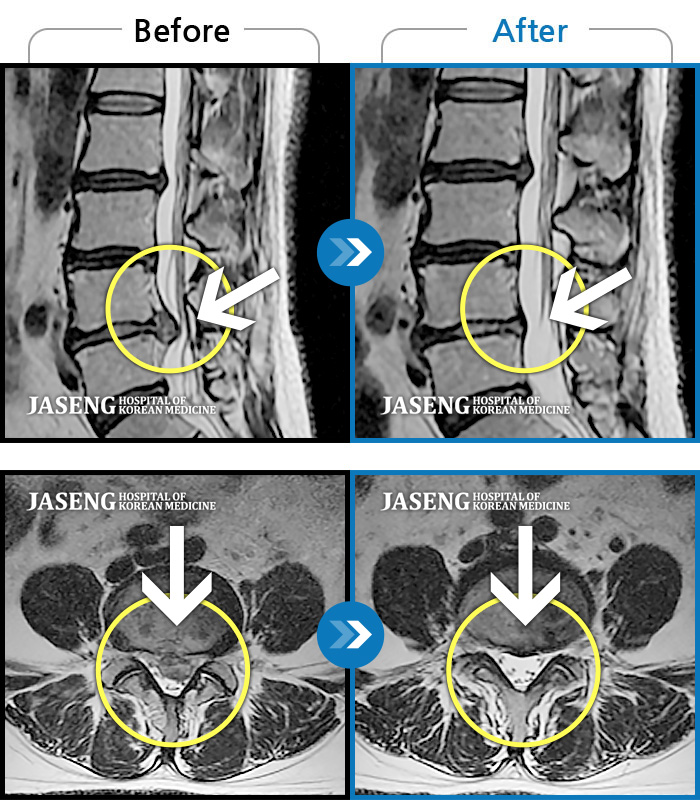

허리디스크

안산 · 김민수 원장

어떤 자세에도 통증이 지속되었다.

촬영시기

2018.10.25 ~ 2024.06.19

2024.07.31

조회수 509